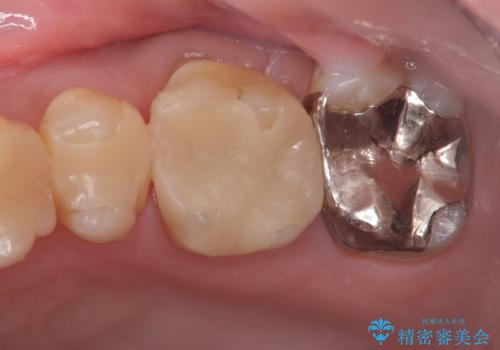

左上7のメタルインレーを除去|セラミッククラウンで自然な美しさと機能回復

- 患者様は、左上7のメタルインレー(銀の詰め物)の見た目が気になるとのことで来院されました。診察したところ、メタルインレーの下にむし歯の再発リスクがあることも確認。より審美性と耐久性を高めるため、メタルインレーを除去し、セラミッククラウンで補綴する治療計画を立てました。